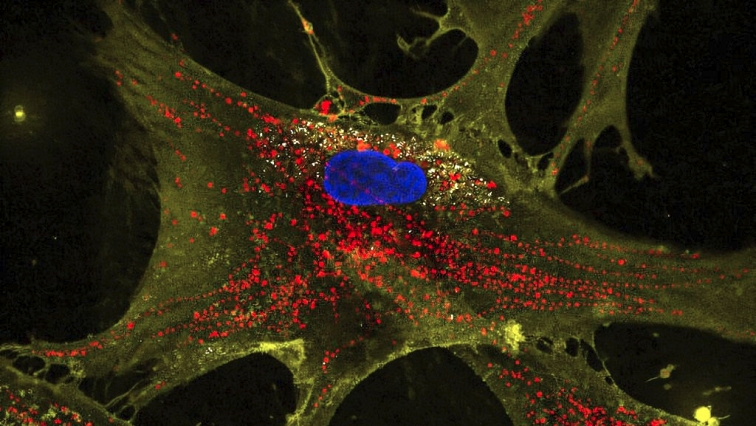

The study, published in Proceedings of the National Academy of Sciences, used a combination of microscopic flower-shaped particles — called nanoflowers — and stem cells. In the presence of these nanoflowers, the stem cells produced twice the normal amount of mitochondria. When these boosted stem cells were placed near damaged or aging cells, they transferred their surplus mitochondria to their injured neighbors.

While cells naturally exchange some mitochondria, the nanoflower-boosted stem cells — nicknamed mitochondrial bio factories — transferred two to four times more mitochondria than untreated ones.